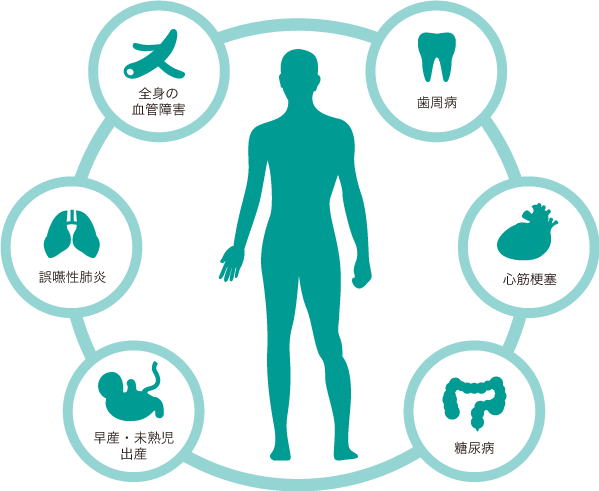

歯周病はお口の中だけの病気?

■歯周病で引き起こされる病気があります。

■糖尿病・細菌性心内膜炎・血管障害などのリスクが上がります。

■また、早産の危険性が高まります。

■高齢者の方は誤嚥性肺炎のリスクも上がります。

■歯周病を治すことは全身の健康に繋がっているのです。

歯周病菌で引き起こされる病気

糖尿病・細菌性心内膜炎・心筋梗塞・血管障害・誤嚥性肺炎・早産・未熟児出産等